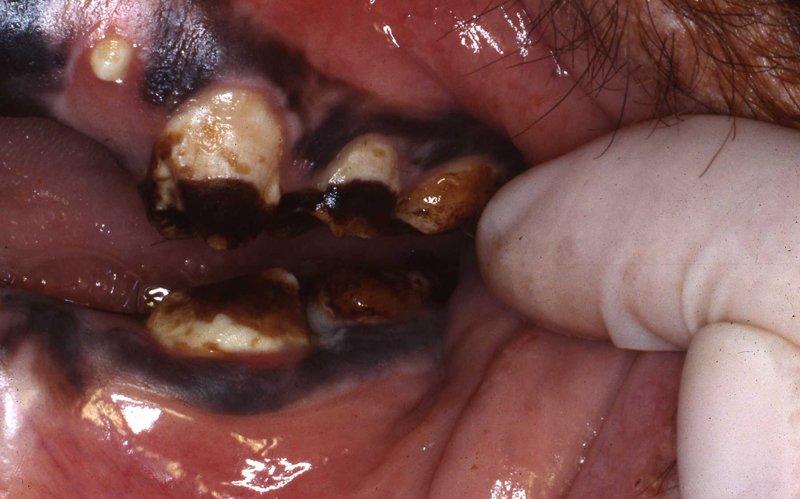

Most or our orangutans however, have had chronic, serious periodontal disease. All of our males have eventually lost all their teeth due to periodontal disease. That has not been the case with the females. We are not the only zoo that has had the chronic periodontal problems with orangutans. See Dr. Norm Stollers' paper: In the typical orangutan case that I have dealt with, there is not much accumulation of plaque or calculus. However, deep periodontal pocketing and bone loss progresses until the teeth become very mobile. I have not observed much bleeding in the most severe of these cases. We discussed preventive strategies and even tried chlorhexidine gluconate rinses to subdue the disease process. However, the orangs did not accept the products, probably due to the taste.

I believe that there is very likely some genetic component to the periodontal disease prevalence in our orangutan lineage. Most of them that we have had are crosses of Sumatran and Borneo genetic lines. And again, with what I have been able to learn about their wild diets is that it is very different than what can be offered in captivity in this part of the world.